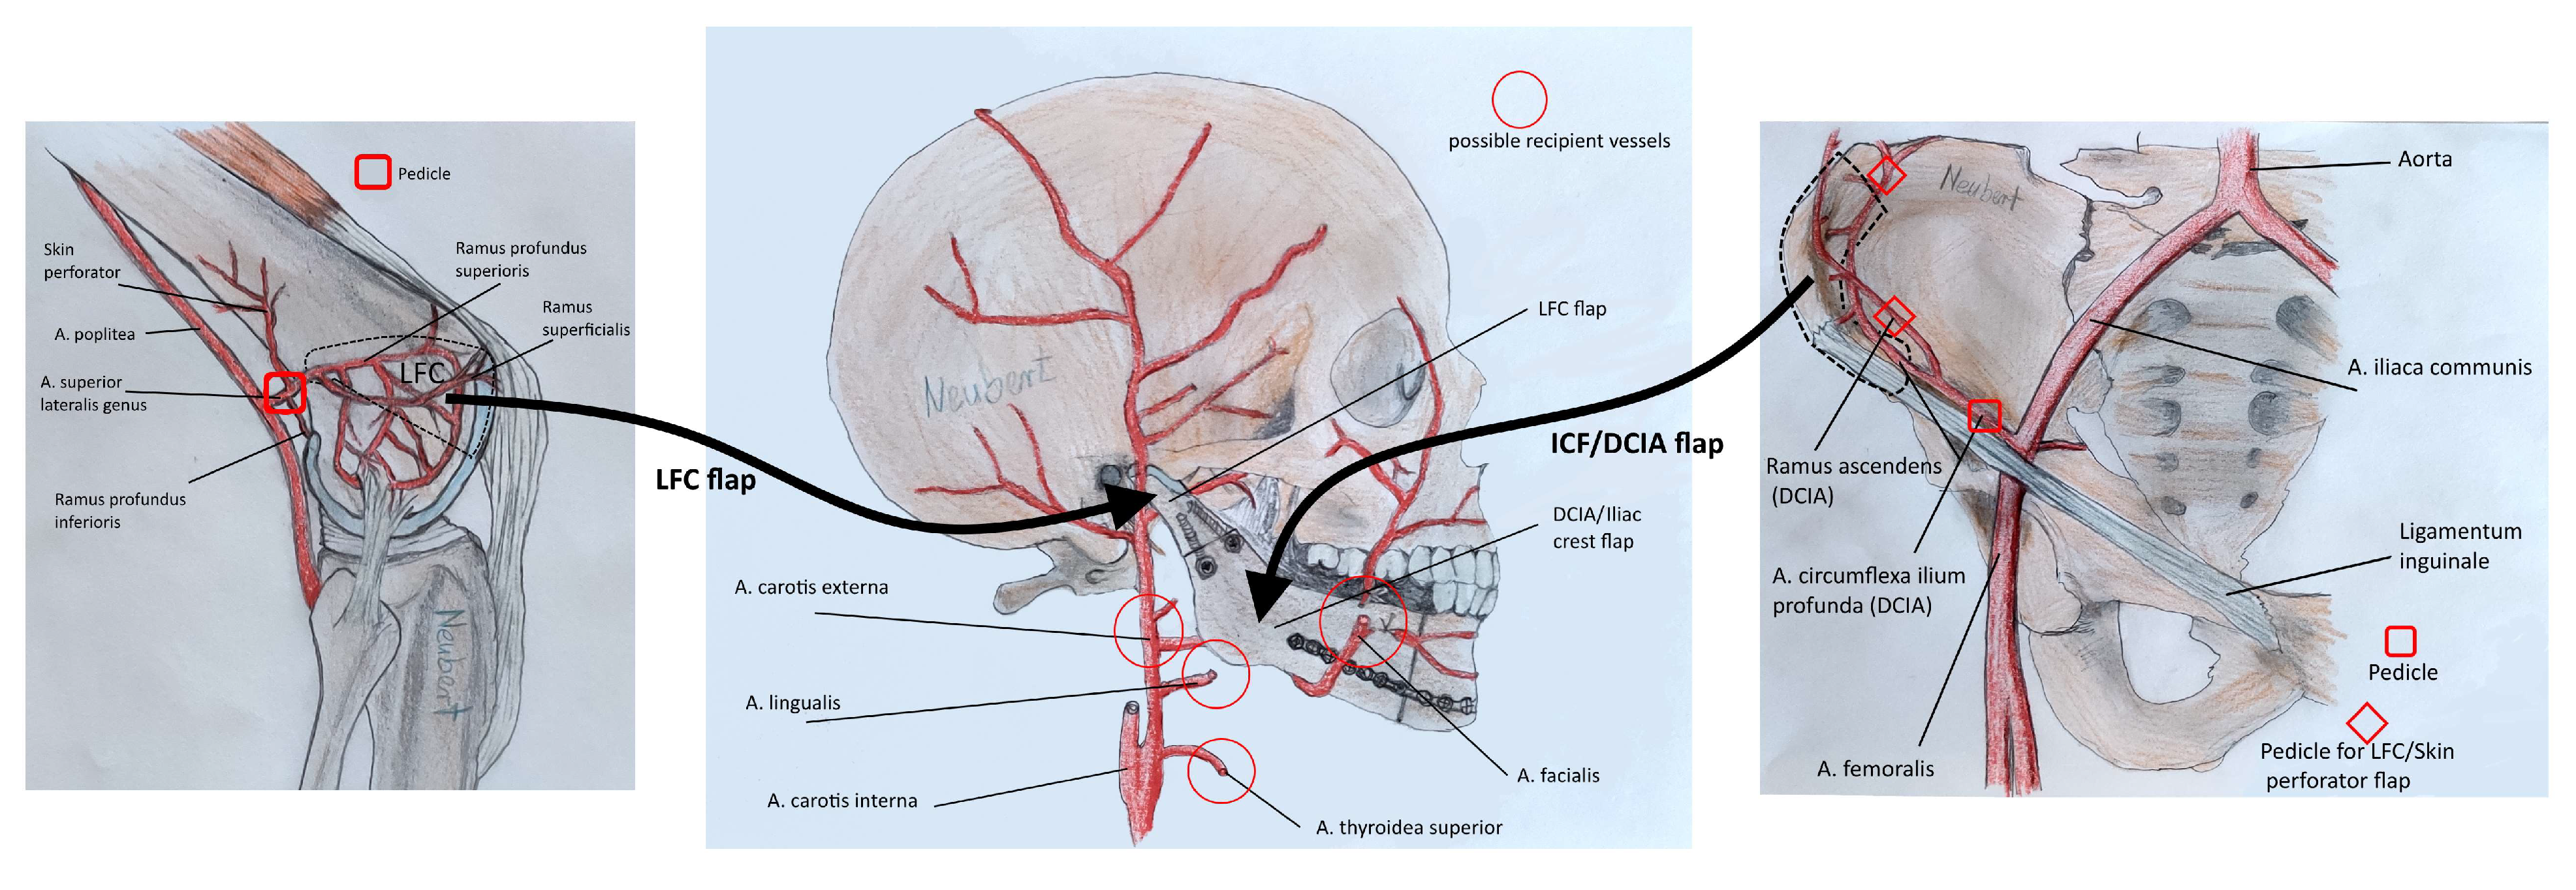

2.2. Surgical Procedure

- Enzinger, S.; Bürger, H.; Gaggl, A. Reconstruction of the mandibular condyle using the microvascular lateral femoral condyle flap. Int. J. Oral. Maxillofac. Surg. 2018, 47, 603–607. [Google Scholar] [CrossRef] [PubMed]

- Parvizi, D.; Vasilyeva, A.; Wurzer, P.; Tuca, A.; Lebo, P.; Winter, R.; Clayton, R.P.; Rappl, T.; Schintler, M.V.; Kamolz, L.-P.; et al. Anatomy of the vascularized lateral femoral condyle flap. Plast. Reconstr. Surg. 2016, 137, 1024e–1032e. [Google Scholar] [CrossRef] [PubMed]

- Morsy, M.; Sur, Y.J.; Akdag, O.; Eisa, A.; El-Gammal, T.A.; Lachman, N.; Moran, S.L. Anatomic and high-resolution computed tomographic angiography study of the lateral femoral condyle flap: Implications for surgical dissection. J. Plast. Reconstr. Aesthet. Surg. 2018, 71, 33–43. [Google Scholar] [CrossRef]